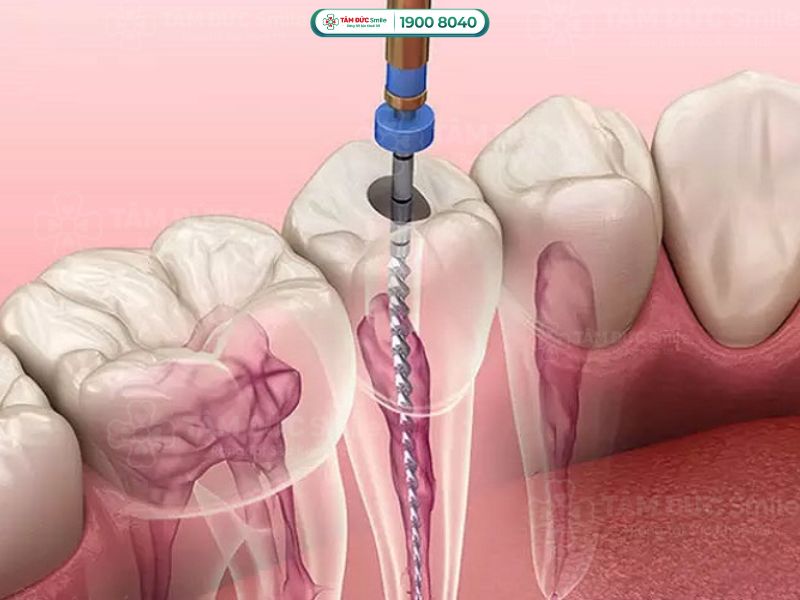

Lấy tủy răng, hay còn gọi là điều trị tủy răng, là thủ thuật nhằm loại bỏ tủy răng bị viêm nhiễm hoặc hoại tử. Lấy tủy răng nhằm mục đích sau:

Lấy tủy răng là thủ thuật nhằm loại bỏ tủy răng bị viêm nhiễm hoặc hoại tử